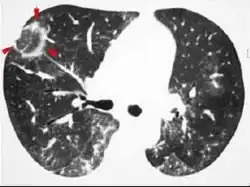

CT image in patient with COVID-19 showing bilateral ground-glass opacities at the periphery of both lungs.

Ground-glass opacity is among the most common imaging findings in patients with confirmed COVID-19.[16][17] One systematic review found that among patients with COVID-19 and abnormal lung findings on CT, greater than 80% had GGOs, with greater than 50% having mixed GGOs and consolidation.[16] GGOs with mixed consolidation has most often been found in elderly populations.[18] Several studies have described a pattern among initial, intermediate, and hospital discharge imaging findings in the disease course of COVID-19. Most commonly, initial CT imaging reveals bilateral GGOs at the periphery of the lungs. During initial stages, this is most often found in the lower lobes, although involvement of the upper lobes and right middle lobe has also been reported early in the disease course.[16][18] This is in contrast to the two similar coronaviruses, SARS and MERS, which more commonly involve only one lung on initial imaging.[19][20] As the COVID-19 infection progresses, GGOs typically become more diffuse and often progress to consolidation.[11][18] This is sometimes accompanied by the development of a crazy paving pattern and interlobular septal thickening.[18] In many cases the most severe pulmonary CT abnormalities occurred within 2 weeks after symptoms began.[17] At this point, many individuals begin showing resolution of consolidation and GGOs as symptoms improve. However, some patients have worsening symptoms and imaging findings, with further increase in septal thickening, GGOs, and consolidation. These patients may develop lung "white-out" with progression to acute respiratory distress syndrome (ARDS) requiring treatment escalation.[17][21]

Preliminary reports have shown many patients have residual GGOs at time of discharge from the hospital. Due to the novelty of COVID-19, large studies investigating the long-term pulmonary CT changes have yet to be completed. However, long-term pulmonary changes have been seen in patients after recovery from SARS and MERS, suggesting the possibility of similar long-term complications in patients who have recovered from acute COVID-19 infection.[22]